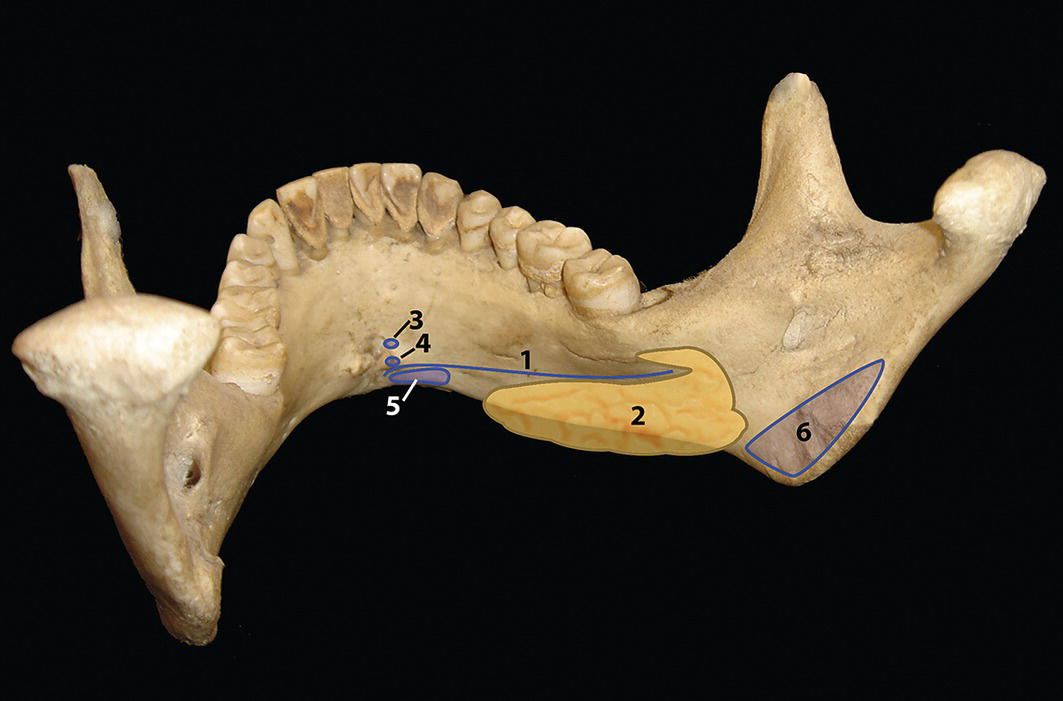

The morphology of the upper aspect of the neck and its transition with the submental region has a major impact on the aesthetics of the lower face. The anterior part of the neck extends no higher than the inferior border of the mandible. The hyoid bone is connected to the mandible by a thin sheet of muscle, the mylohyoids, which form the upper limit of the anterior part of the neck and separate the mouth from the neck. Superficially (i.e. below the mylohyoids) lies the anterior belly of digastric, while lying above it, half hidden under the mandible in the submandibular fossa, is the submandibular salivary gland (Figure 21.1). These structures are covered in by the investing layer of deep cervical fascia, which is attached to the hyoid bone and the inferior border of the mandible. The platysma muscle lies in the subcutaneous tissues. It forms a broad, flat sheet, extending from the deep fascia over the upper part of pectoralis major and the most anterior part of deltoid to the inferior border of the mandible, with some fibres reaching the lateral part of the lower lip. The sternocleidomastoid muscle forms a prominent neck landmark and may be made to stand out by turning the head towards the opposite side against resistance. The two heads of origin are from the sternum and medial one‐third of the clavicle; its attachment is to the mastoid process, which forms a readily visible and palpable bony landmark behind the lobe of the ear (Figure 21.2). Figure 21.1 Submental anatomy in relation to the mandible, with muscle attachments: Despite its importance in facial aesthetics, there is much confusion in terminology relating to the description and analysis of the submental‐cervical region. For example, the cervicomental angle has been described by perhaps half a dozen different methods, depending on the describing authority. Appropriate terminology is essential for the evaluation and accurate description of submental‐cervical aesthetics (Figure 21.3). Figure 21.2 Profile view of the face and neck with superimposed bony and muscular outlines: Cervical point (C‐point or ‘point C’): The innermost (posterior‐superior) point between the submental plane and the anterior aspect of the neck in the midsagittal plane, located at the intersection of lines drawn tangent to the submental region and the anterior neck. Submental plane: A plane or line constructed between the cervical point (C‐point) and the most inferior point on the chin (soft tissue menton, Me’). If C‐point cannot be defined, the submental plane is drawn tangent to the submental contour passing through soft tissue menton. The submental plane is referred to as the ‘throat’ plane by some authorities; the submental length (distance from C‐point to menton) is therefore sometimes referred to as the ‘throat length’. Cervical plane: A plane or line drawn tangent to the anterior soft tissue contour of the neck above and below the thyroid prominence. Figure 21.3 Submental plane, cervical plane and cervical point (C‐point). A thorough understanding of the aetiological factors involved in creating a poor aesthetic contour of the submental‐cervical region is required in order to diagnose and appropriately plan the correction of the aesthetic submental‐cervical angles and contour. The tonicity of the submental‐cervical skin, the muscular support of the neck, the isolated fatty deposits in the submental‐cervical region, the skeletal framework of the mandible and chin, and the spatial position of the hyoid bone are all important parameters in the aesthetic analysis of the submental‐cervical region. An undesirable submental‐cervical contour may result from: It is paramount that the clinical evaluation is undertaken with the patient in natural head position (NHP). Even a small degree of upward or downward tilting of the head must be avoided as it may have a profound effect on the contour of the submental‐cervical region. A number of parameters may be analysed in the clinical evaluation of the submental‐cervical region: Mandibular and/or chin deficiency in the sagittal plane, and/or posterior (downward and backward) rotation of the mandible, often secondary to vertical maxillary excess, may contribute to the undesirable aesthetic appearance of the submental‐cervical region (Figure 21.4). It is helpful to have the ‘Class II skeletal pattern’ patient posture the mandible forward to a more normal sagittal position, which will concurrently stretch the submental soft tissues. If this manoeuvre improves the submental‐cervical aesthetics visually, and tightens the submental soft tissues to palpation, then correction of the underlying skeletal discrepancy is likely to improve the submental‐cervical aesthetics (Figure 21.5). Figure 21.4 Class II jaw relationship due to mandibular deficiency and significant compensatory proclination of the mandibular incisor teeth; the submental‐cervical angle is increased. Figure 21.5 (A) Patient with Class II jaw relationship due to mandibular deficiency. (B) Posturing the mandible forward to a more normal sagittal position will concurrently stretch the submental soft tissues. Figure 21.6 Skin laxity test. The converse is also true. Surgical procedures to set back the mandible, or set down the maxilla causing posterior mandibular rotation, will tend to have undesirable consequences on submental‐cervical aesthetics (see Figure 19.22). The patient must be informed of these potential untoward consequences of orthognathic surgery, and should be advised of the possible future need for aesthetic surgical procedures of the submental‐cervical region. The laxity of the submental‐cervical skin may be evaluated by the skin laxity test: the clinician stands behind the patient and gently pulls the soft tissues upward and backward just inferior and anterior to the ear, simulating a neck lift (Figure 21.6). If the soft tissues are easily displaced upward there is increased laxity of the skin, termed redundant skin.1 If following this manoeuvre there is still submental fullness, the patient has redundant skin and excessive submental‐cervical adiposity. Reduced tonicity of the platysma may contribute significantly to submental fullness.2,3 In addition, the platysma muscle may or may not merge anatomically across the midline. Frequently, excessive submental fullness results not only from redundant skin but from the redundant medial borders of the platysma muscle that fail to meet in the midline. Increased submental‐cervical fat accumulation may be independent of generalized body fat; in some patients subcutaneous fat accumulation in this region may remain despite extensive weight loss. In younger patients the fat usually accumulates between the skin and the platysma muscle. In older patients, the fat may accumulate both deep and superficial to the platysma (Figure 21.9). The quantity of submental fat may be estimated by the submental pinch test: the submental soft tissues are gently gripped between the thumb and index finger.1 This manoeuvre should be performed with the patient both in NHP and with the head extended and contracting the platysma muscle; in this way the clinician may determine whether the submental fat is predominantly supraplatysmal or subplatysmal. Figure 21.7 Platysma view: With the head tilted slightly back in frontal view, grimacing and clenching the teeth will induce contraction of the platysma muscle. The muscular fascicles of the platysma become visible beneath the skin. Figure 21.8 Platysmal bands may be evident in repose in an ageing neck. Figure 21.9 Submental adiposity. Figure 21.10 The definition of the inferior border of the mandible is an important aesthetic parameter as it defines the demarcation between the face and neck. (Detail, Woman’s Head, Leonardo da Vinci, c. 1470–76, Galleria degli Uffizi, Florence.) The definition of the inferior border of the mandible, from the chin to the gonial angle, is an important aesthetic parameter, as it defines the demarcation between the face and neck (Figure 21.10). In frontal view, the transition from the upper aspect of the neck to the inferior border of the mandible has a subtle hourglass appearance, with its superior aspect being well defined by the concavity immediately below the inferior mandibular borders (Figure 21.11).1 The soft tissues of the neck normally closely adhere to the structures underlying them. Lack of definition of the inferior mandibular border may be due to increased soft tissue laxity, fat accumulation, mandibular/chin deficiency or hyoid bone sag. Figure 21.11 In frontal view, the transition from the upper aspect of the neck to the inferior border of the mandible has a subtle hourglass appearance. The submandibular salivary gland envelopes the posterior border of the mylohyoid muscle, half hidden in the submandibular fossa on the medial aspect of the mandible (see Figure 21.1). Submandibular fullness may result from an increase in size of the submandibular gland, laxity of the neck fascial layer or submandibular gland ptosis. Rhytidectomy and platysma plication address this problem indirectly by increasing the fascial support for the gland. However, patients may develop a more noticeable submandibular fullness as the removal of submental fat unmasks the ptotic gland. Partial or complete submandibular gland resection provides definite improvement of submandibular fullness resulting from glandular hypertrophy or ptosis, but may be considered too radical for a patient with a normal‐sized, ptotic submandibular gland. Guyuron et al.4 have described the basket submandibular gland suspension technique, directly supporting the gland onto the inner aspect of the inferior surface of the mandible with a strong piece of fascia. This technique helps eliminate submandibular fullness in patients with normal‐sized, ptotic glands. Resection remains the treatment of choice for the correction of glandular hypertrophy. Figure 21.12 Of the ‘six visual criteria’ of the profile view for ‘success in restoring the youthful neck’, the following are demonstrated: 1 Distinct inferior mandibular border 4 Visible anterior border of sternocleidomastoid muscle 5 Submental‐cervical (submental‐neck) angle between 105° and 120° 6 Sternocleidomastoid‐submental plane (SM‐SM) angle approximately 90°